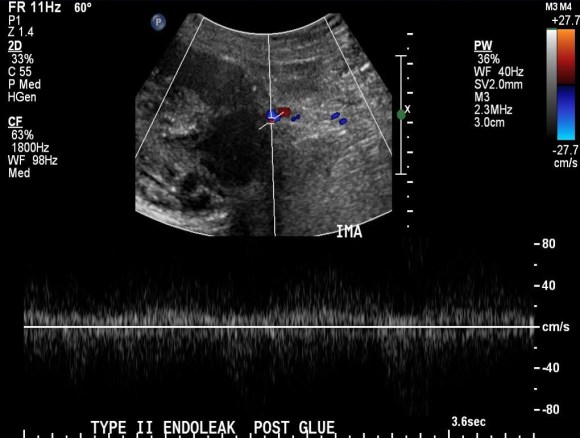

The embolization with NBCA sealed the IMA and the cavity in the AAA sac. This was checked with intraoperative duplex, done with a transabdominal aortic probe.

Transabdominal aortic duplex is easier on sleeping patient and potentially gives more information than arteriography alone. The patient in followup had no endoleak and demonstrated sac shrinkage.